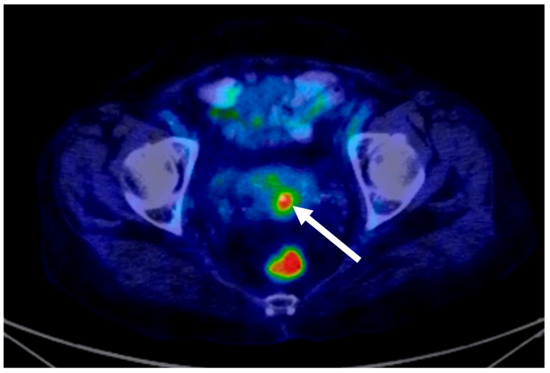

| 11. Weiyan Zhou [18] | 2016 | 1/31 | − | (DLBCL) | 6 × R-CHOP | 12 months/PET-CT/MRI |